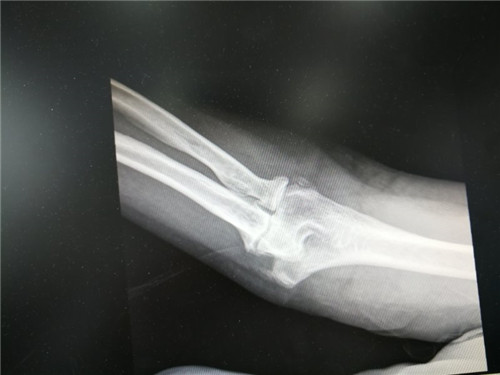

近日,骨三科收治一例56岁女性右肘关节骨性关节炎患者,患者五年前无明显诱因出现右肘关节肿胀、疼痛,活动受限,伴右手疼痛,活动后加剧,休息后缓解,疼痛反复发作。在骨三科行肘关节镜手术获得成功。半年前,患者摔伤后在外院就诊,肘关节处外用膏药治疗效果不佳。一周前前来我院行X线检查提示:右肘关节骨性关节炎,门诊检查后以"右肘关节骨关节炎"诊断收住骨三科。

患者入院时查体右肘皮肤完好,轻度肿胀,右肘关节屈曲外翻畸形、肘关节前侧、后侧压痛,前侧可触及质硬包块,肘关节活动度50~100°。副主任医师胡洪波接诊后建议手术治疗,诊断为右肘关节骨性关节炎4期,经充分沟通后于1月3日与主治医师李政为患者施行"右肘关节镜下游离体摘除关节松解微创手术。"术后患者屈伸活动度明显改善,疼痛消失,生活基本恢复正常。